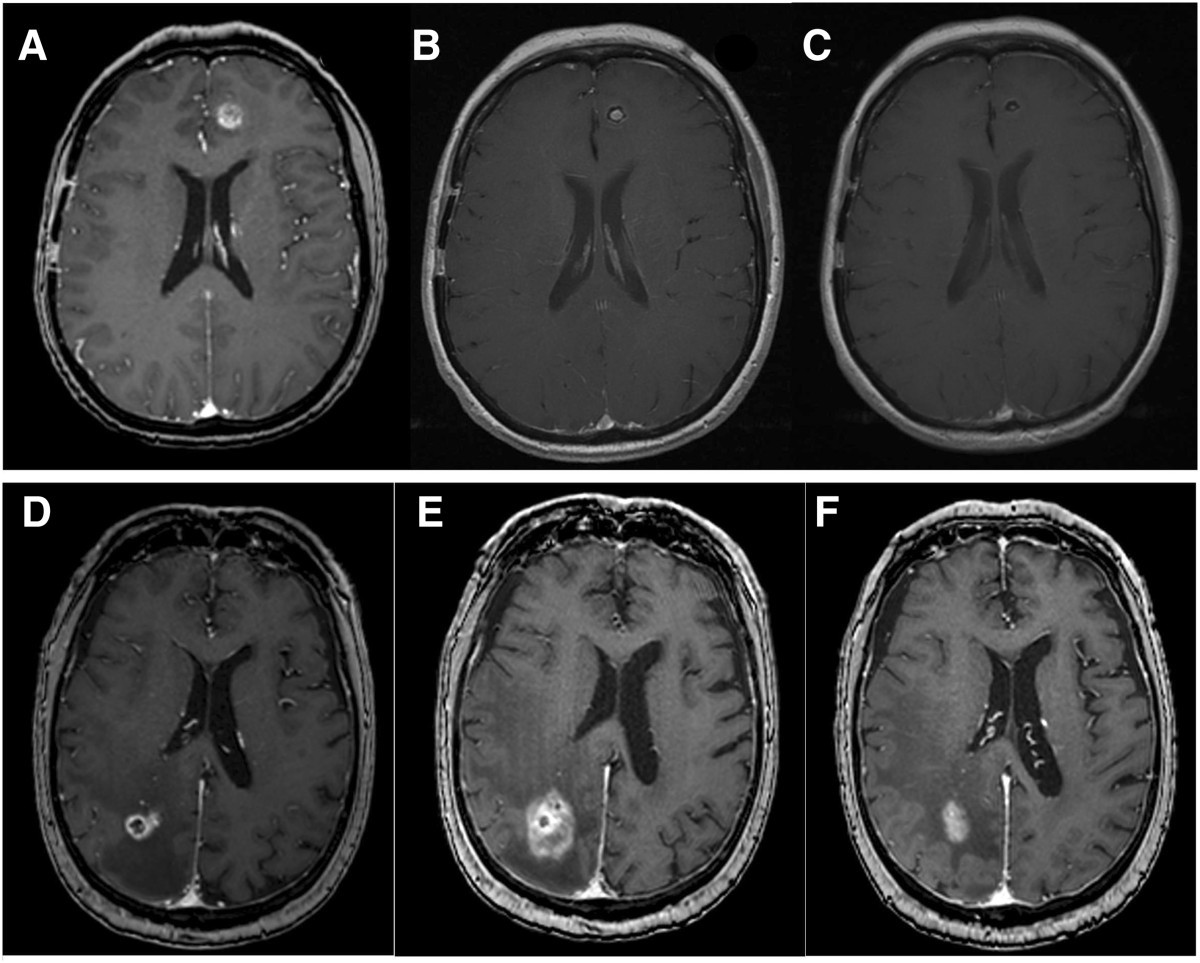

Brain metastases are the most frequently diagnosed intracranial neoplasms in adults, with an annual incidence estimated at 200,000 cases in the usa alone 1, an incidence 10 times greater than. To identify the incidence, recurrence pattern and prognosis of brain metastases (bm) among women with metastatic triple negative breast cancer (mtnbc) treated consecutively at a. Read on to know more.

Advanced technologies and treatment options for brain metastases are helping brain metastases treatment.

Advanced technologies and treatment options for brain metastases are helping brain metastases treatment. In the past, outcomes were considered. Current status and future pullen lc. Read on to know more.